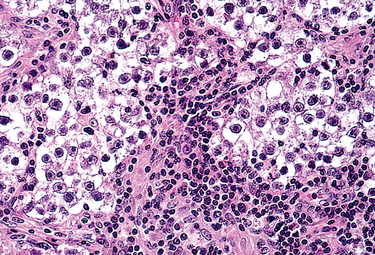

The dysgerminoma is best considered as the ovarian counterpart of the seminoma of the testis. Similar to the seminoma, it is composed of large vesicular cells having a clear cytoplasm, well-defined cell boundaries, and centrally placed regular nuclei. Dysgerminomas account for about 2% of all ovarian cancers yet form about half of malignant germ cell tumors. They may occur in childhood, but 75% occur in the second and third decades. Some occur in patients with gonadal dysgenesis, including pseudohermaphroditism. Most of these tumors have no endocrine function. A few produce elevated levels of chorionic gonadotropin and may have syncytiotrophoblastic giant cells on histologic examination. Like seminomas, dysgerminomas express Oct3, Oct4, and Nanog.99 These transcription factors are implicated in maintenance of pluripotency. They also express the receptor tyrosine kinase c-KIT. These proteins are useful diagnostic markers and, in the case of c-KIT, may also serve as a therapeutic target.100

Morphology. Usually unilateral (80% to 90%), most are solid tumors ranging in size from barely visible nodules to masses that virtually fill the entire abdomen. On cut surface they have a yellow-white to gray-pink appearance and are often soft and fleshy. On histologic examination the dysgerminoma cells are dispersed in sheets or cords separated by scant fibrous stroma (Fig. 22-46). As in the seminoma, the fibrous stroma is infiltrated with mature lymphocytes and occasional granulomas. On occasion, small nodules of dysgerminoma are encountered in the wall of an otherwise benign cystic teratoma; conversely, a predominantly dysgerminomatous tumor may contain a small cystic teratoma.

image

FIGURE 22-46 Dysgerminoma showing polyhedral tumor cells with round nuclei and adjacent inflammation.